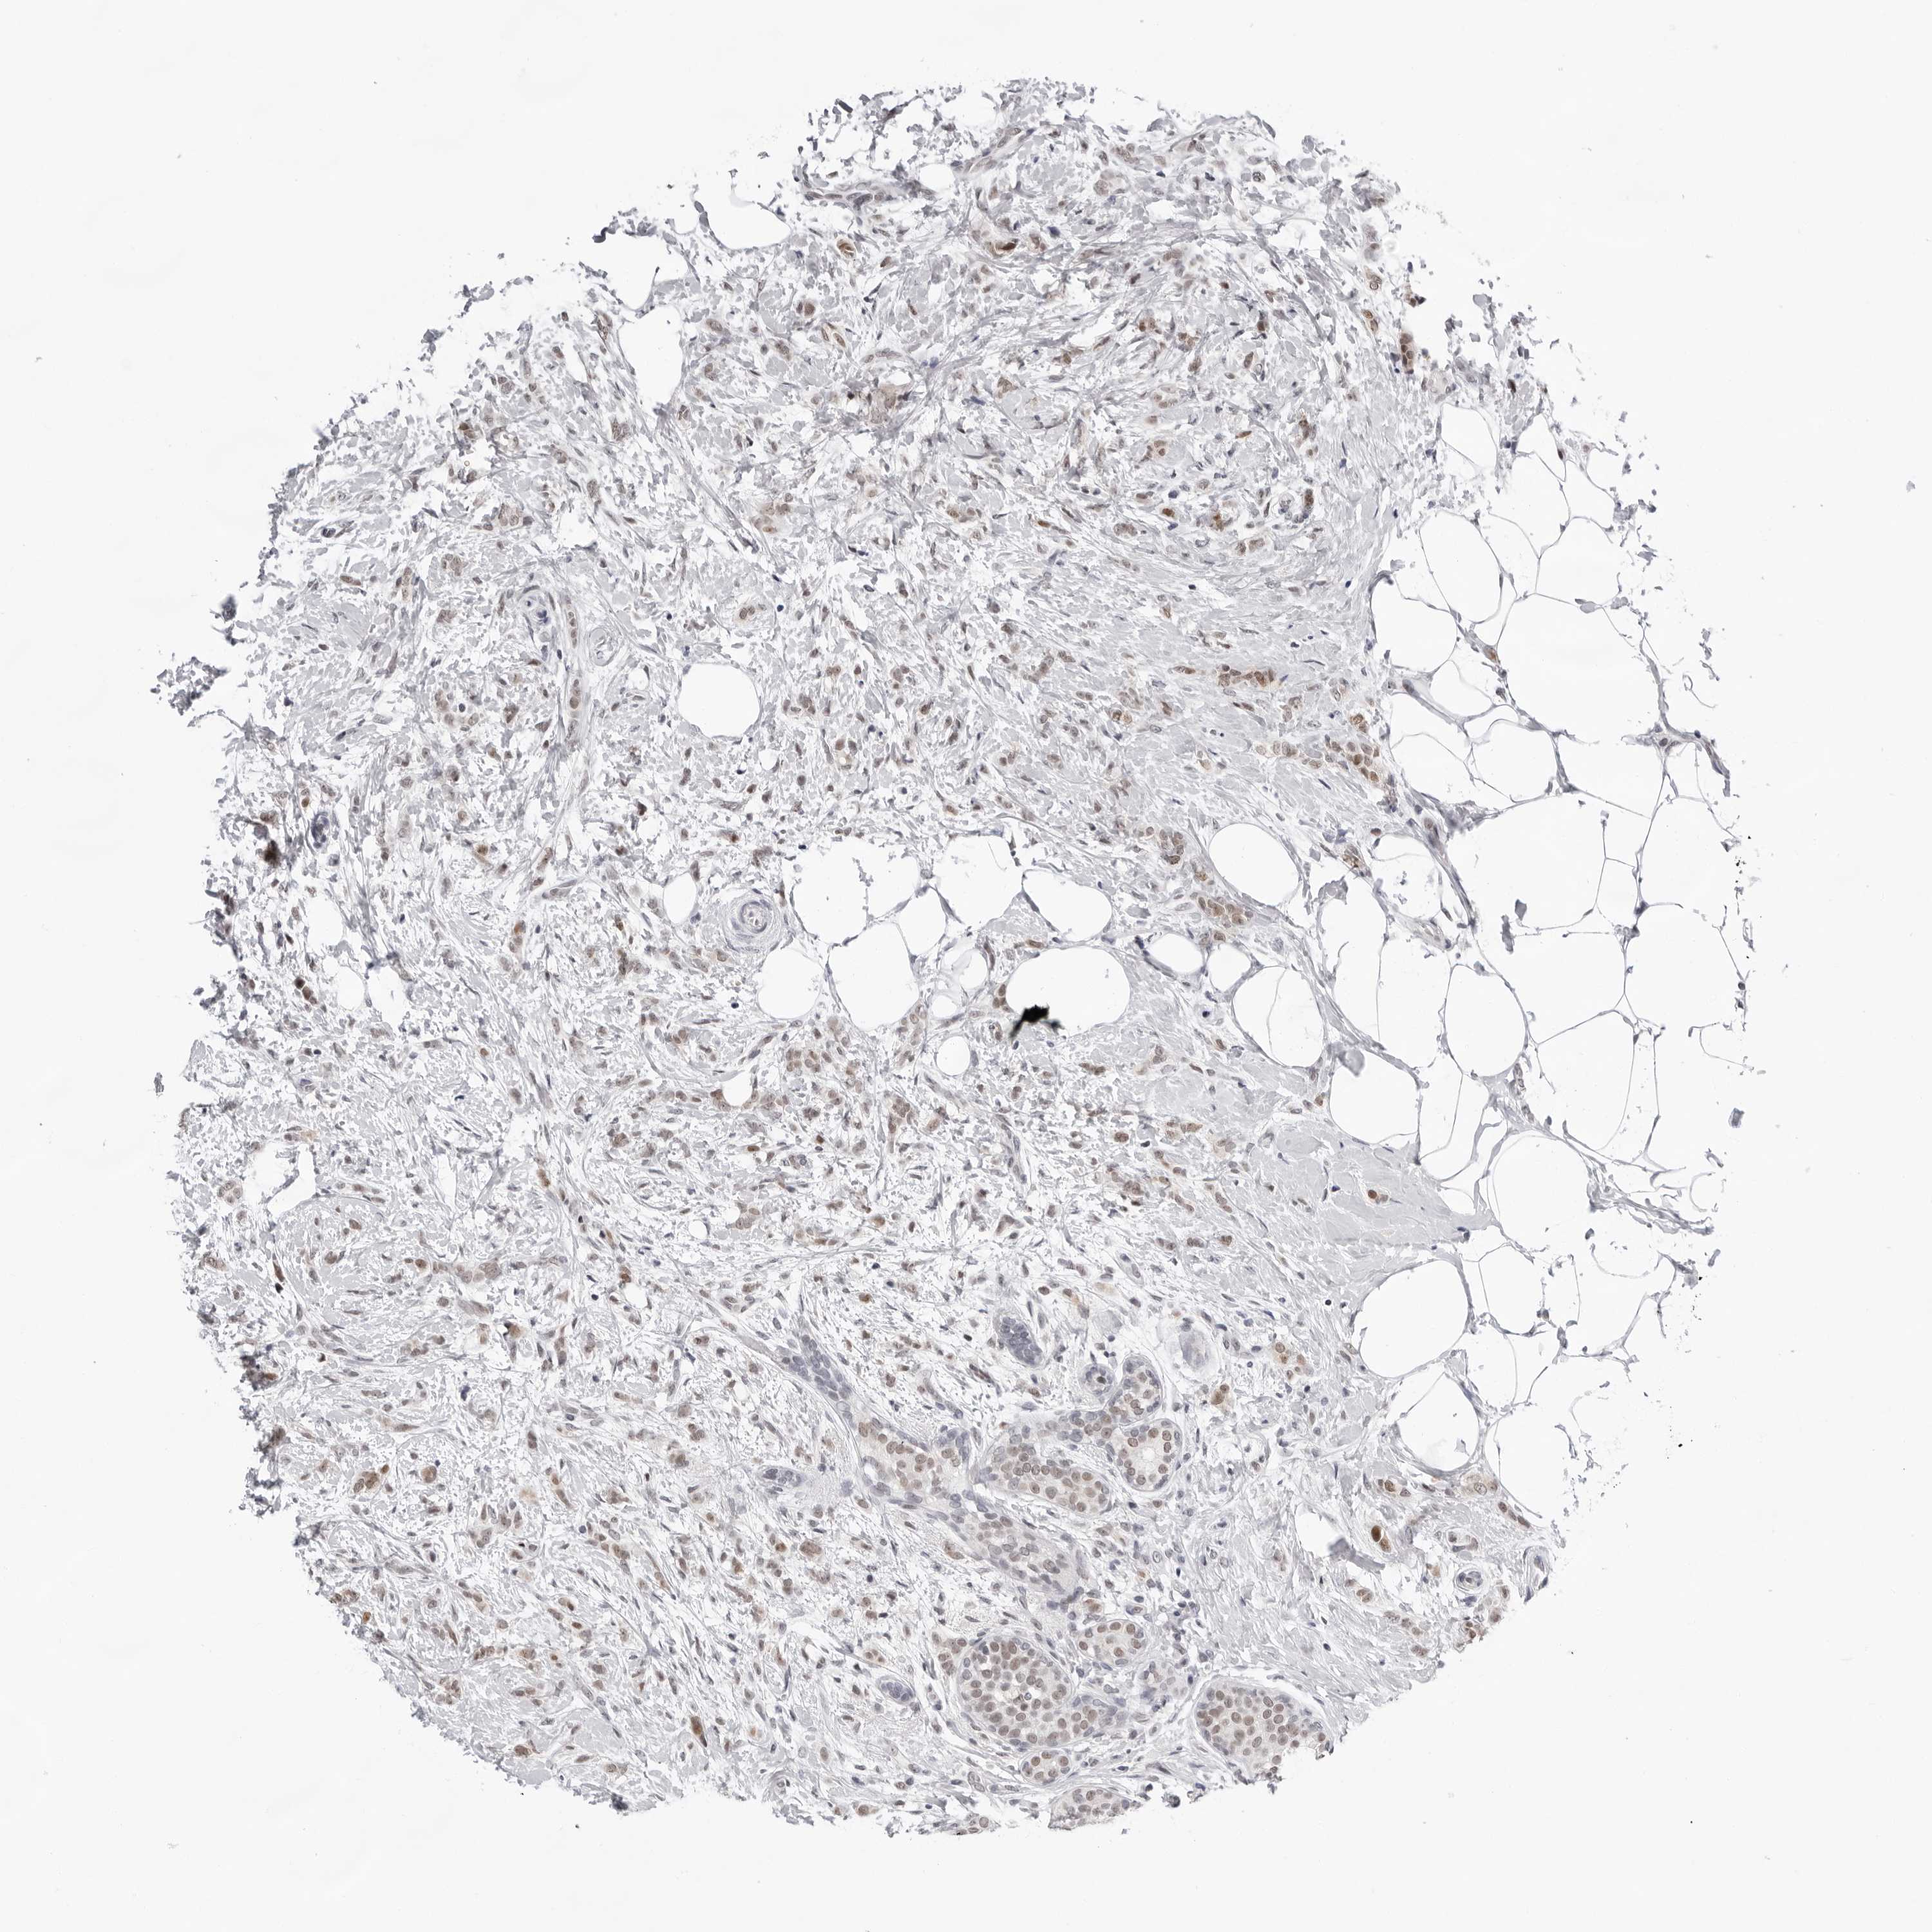

BRCA TCGA BRCA VALIDATION PROTEIN EXPRESSION